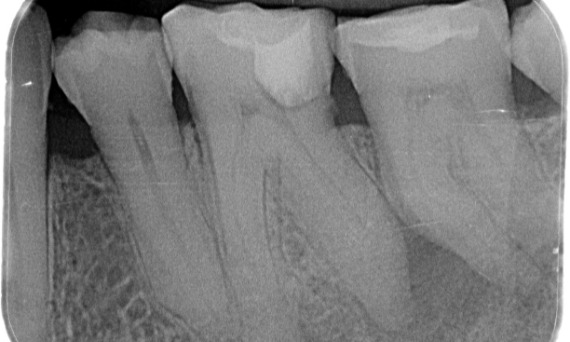

Before: Upon examination, there was a caries lesion related to the lower right first molar. Radiographic examination revealed proximity of the lesion to the pulp horn and combining it with the chief complaint, a final diagnosis of chronic irreversible pulpitis was concluded.

After: Access cavity was done as conservative as possible. TruNatomy was the system of choice due to the young patient’s age. We needed to preserve dentine as much as possible to increase the tooth ability to overcome occlusal load and increase the longevity of the final restoration.

Cairo, Egypt